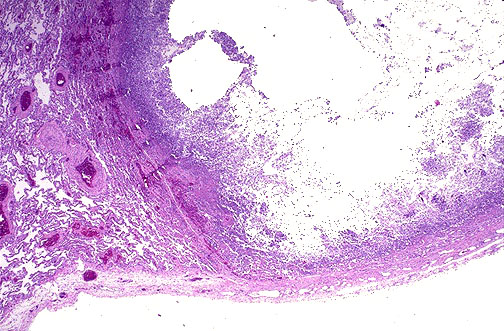

曲霉球最常发生于已经存在的肺空洞内,包括肺结核、支气管扩张、肺囊肿、结节病、组织胞质菌病、强直性脊柱炎、恶性肿瘤等疾病形成的肺空洞,偶尔见于胸膜腔特别外科瘢痕或胸膜粘连形成的腔隔内。曲霉入侵和植入空洞,属于腐物性寄生,仅伴轻微的组织侵犯。生长在空洞内的曲霉球其引流和血供较差。曲霉球本身由曲霉丝缠绕包裹而成。曲霉生长于洞壁,好侵犯局部结构特别是血管,但很少侵犯肺实质或经血管扩散。少数情况下曲霉球可以改变其良性慢性过程而变为侵入性的,甚至可以致命。关于曲霉球的生命周期,有研究表明其早期向腔内生长,最终出现X线上的球形阴影,其中曲霉或为活菌,亦可以有死菌。转归取决于活菌和死菌何者占优势,若局部环境不利于曲霉生长,曲霉最终液化和咳出。死亡曲霉的残留球形病灶偶有钙化。